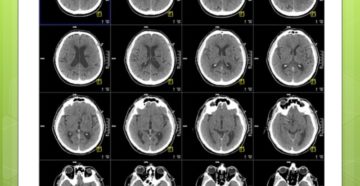

Что лучше КТ или МРТ головного мозга: чем они отличаются – МЕДСИ Компьютерная томография –…